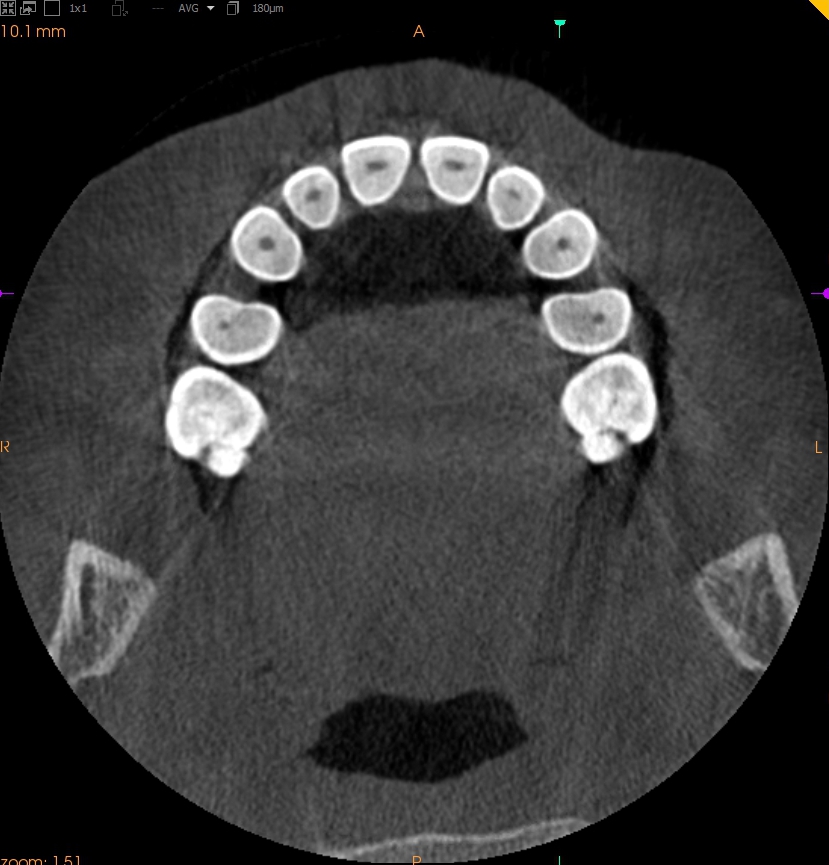

Resorpcja zęba to proces powstania ubytku twardych struktur zęba wywołanego przez osteoklasty bez kontaktu ze środowiskiem jamy ustnej, między innymi na skutek ucisku wywieranego przez ząb zatrzymany. Dla lekarza ortodonty jest istotne ustalenie, czy zęby zatrzymane lub twory nadliczbowe powodują resorpcję zębów stojących w łuku w celu wczesnej eliminacji przyczyny resorpcji. Celem pracy jest przedstawienie opisu przypadku zastosowania tomografii stożkowej w diagnostyce nieprawidłowo położonych zawiązków zębów przedtrzonowych drugich górnych. Stwierdzono, że tomografia stożkowa jest skuteczną metodą oceny wczesnej resorpcji zewnętrznej korzeni zębów.

Tooth resorption is the process of appearing of a defect of hard tissues of teeth caused by osteoclasts not having contact with oral cavity environment, eg. due to mechanical pressure exerted by an impacted tooth. It is essential for an orthodontist whether impacted teeth or supplementary teeth cause resorption of erupted teeth in order to early eliminate the causative factor of the resorption. The aim of the paper is to describe a case report of cone-beam computed tomography (CBCT) in diagnostics of incorrectly located germs of upper second premolars. It was found that CBCT was an efficient method of imaging of early external root resorption.